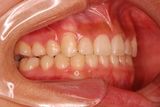

矯正前                 矯正後

治療前 の 左 です 動く矢印治療後 の 左 です

治療前 の 右 です 動く矢印治療後 の 右 です